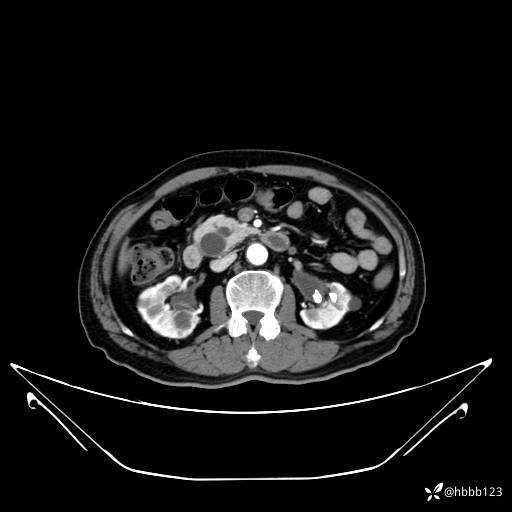

平扫: